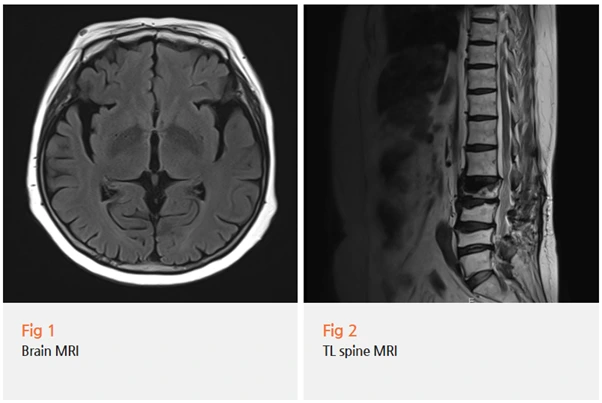

당일 뇌 MRI를 촬영하고,

신경학적 검사와 임상 평가를 종합적으로 시행했어요.

여기에 뇌 MRI를 추가로 시행하는 이유는

다른 뇌질환을 배제하기 위해서입니다.

뇌졸중이나 뇌종양, 정상압 수두증 같은 질환들도

파킨슨병과 유사한 증상을 보일 수 있거든요.

필요한 경우 DAT 스캔이라는 특수 검사를 시행하기도 하는데,

이는 도파민 신경세포의 기능을 직접 평가할 수 있는 검사입니다.